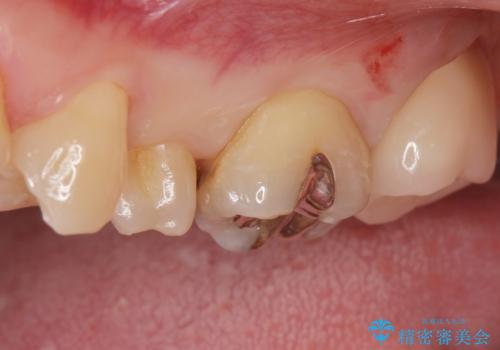

白い被せ物が入りとても満足して頂けました。

セラミックの被せ物は銀歯に比べて虫歯の再発のリスクが低いです。